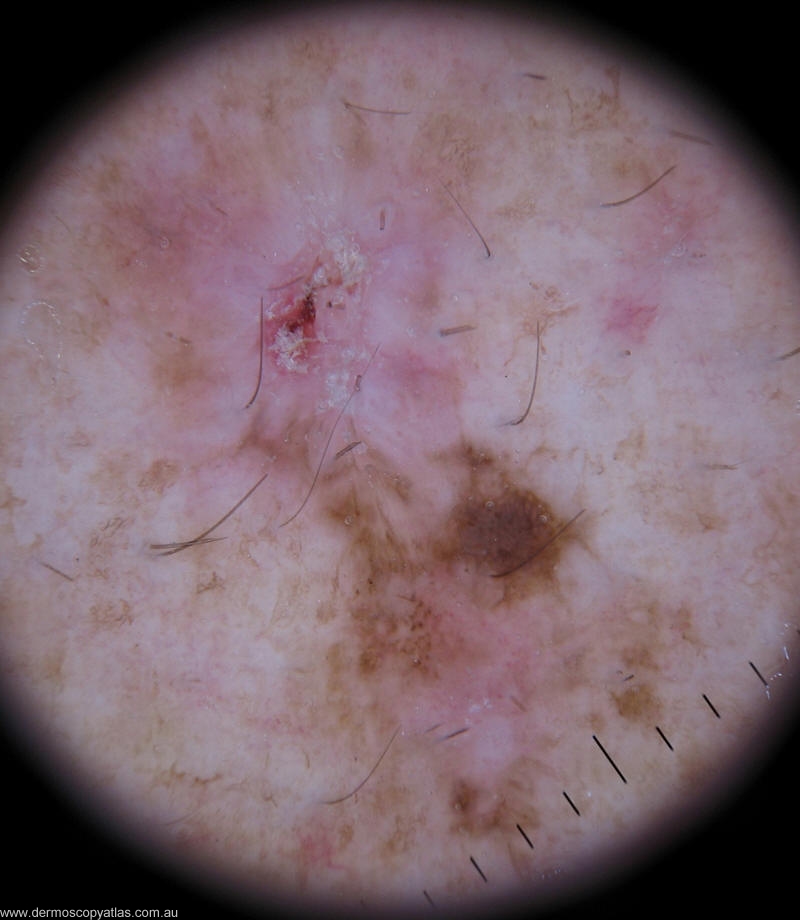

Case 2 52 y.o man presented for his annual melanoma follow up.He has history of Clark Level III melanoma excised from his left flank 15 years ago.Since then he has few BCCs excised from his face and trunk.

Question: What is your diagnosis of this lesion?